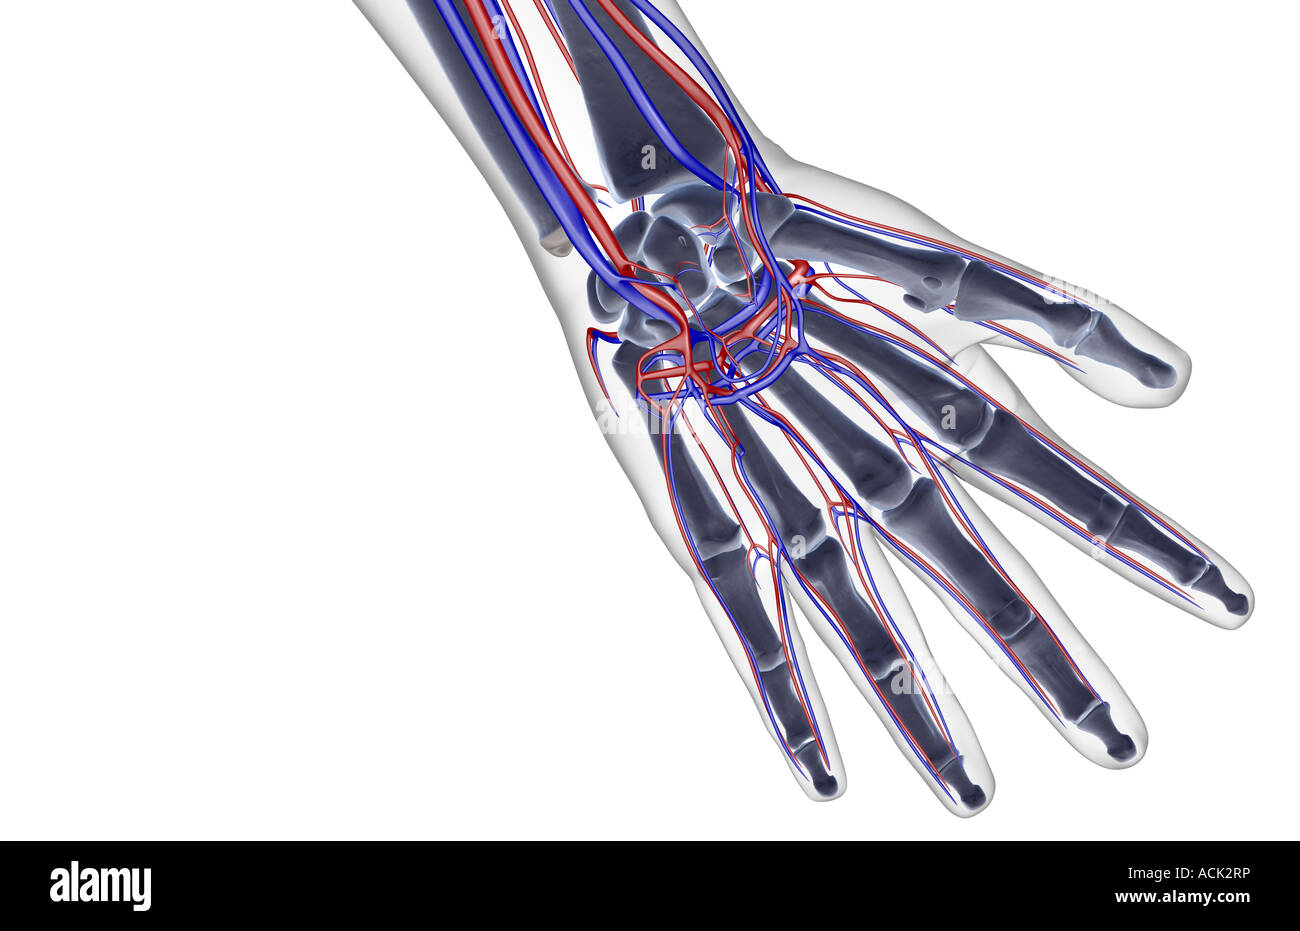

The blood supply of the hand Stock Photohttps://www.alamy.com/image-license-details/?v=1https://www.alamy.com/stock-photo-the-blood-supply-of-the-hand-13175289.html

The blood supply of the hand Stock Photohttps://www.alamy.com/image-license-details/?v=1https://www.alamy.com/stock-photo-the-blood-supply-of-the-hand-13175289.htmlRFACK2RP–The blood supply of the hand